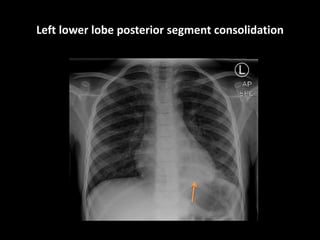

Left lower lobe posterior segment consolidation